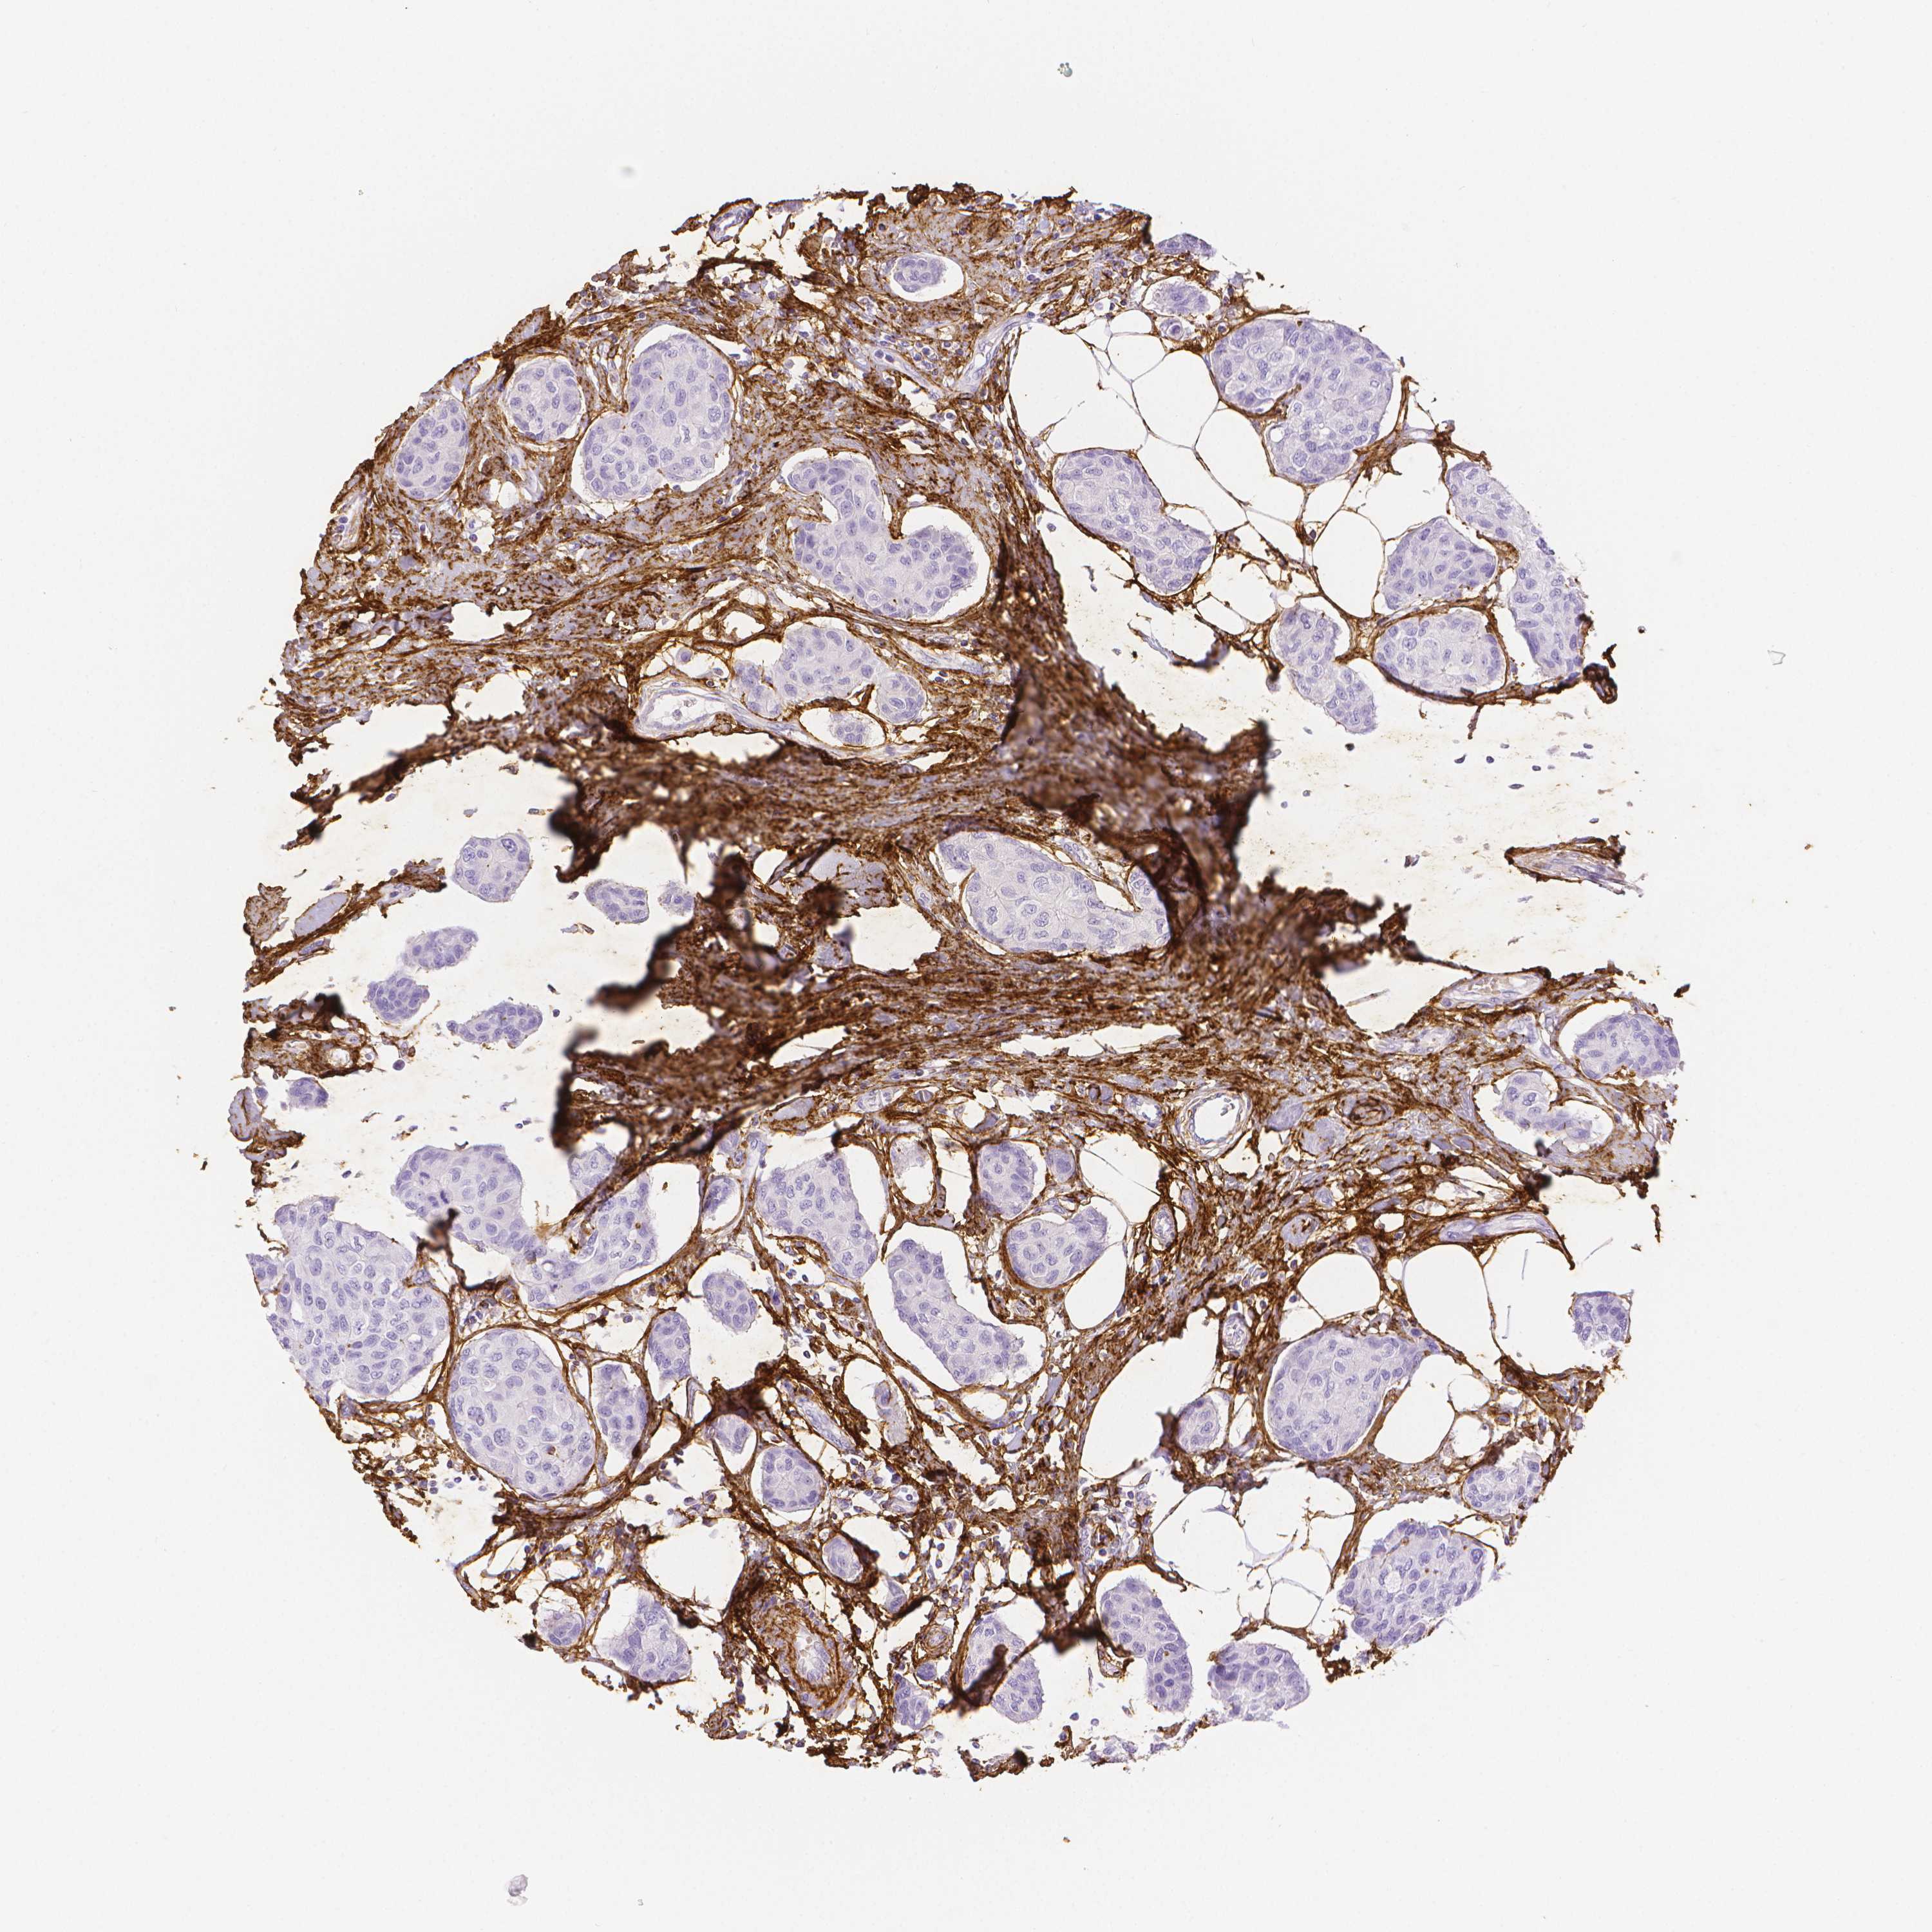

BRCA TCGA BRCA VALIDATION PROTEIN EXPRESSION

ANTIBODIES

AND

VALIDATION